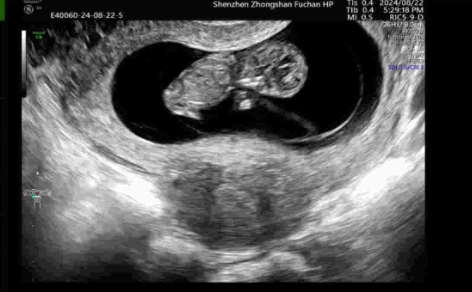

胚胎移植之前,李睿医生建议秦女士做宫腔镜检查,排除“土壤”是否有问题,检查结果提示无异常。 2024年6月,经过医生评估符合移植条件,复苏冷冻胚胎移植,一次成功妊娠,并于2025年2月成功接到小天使。